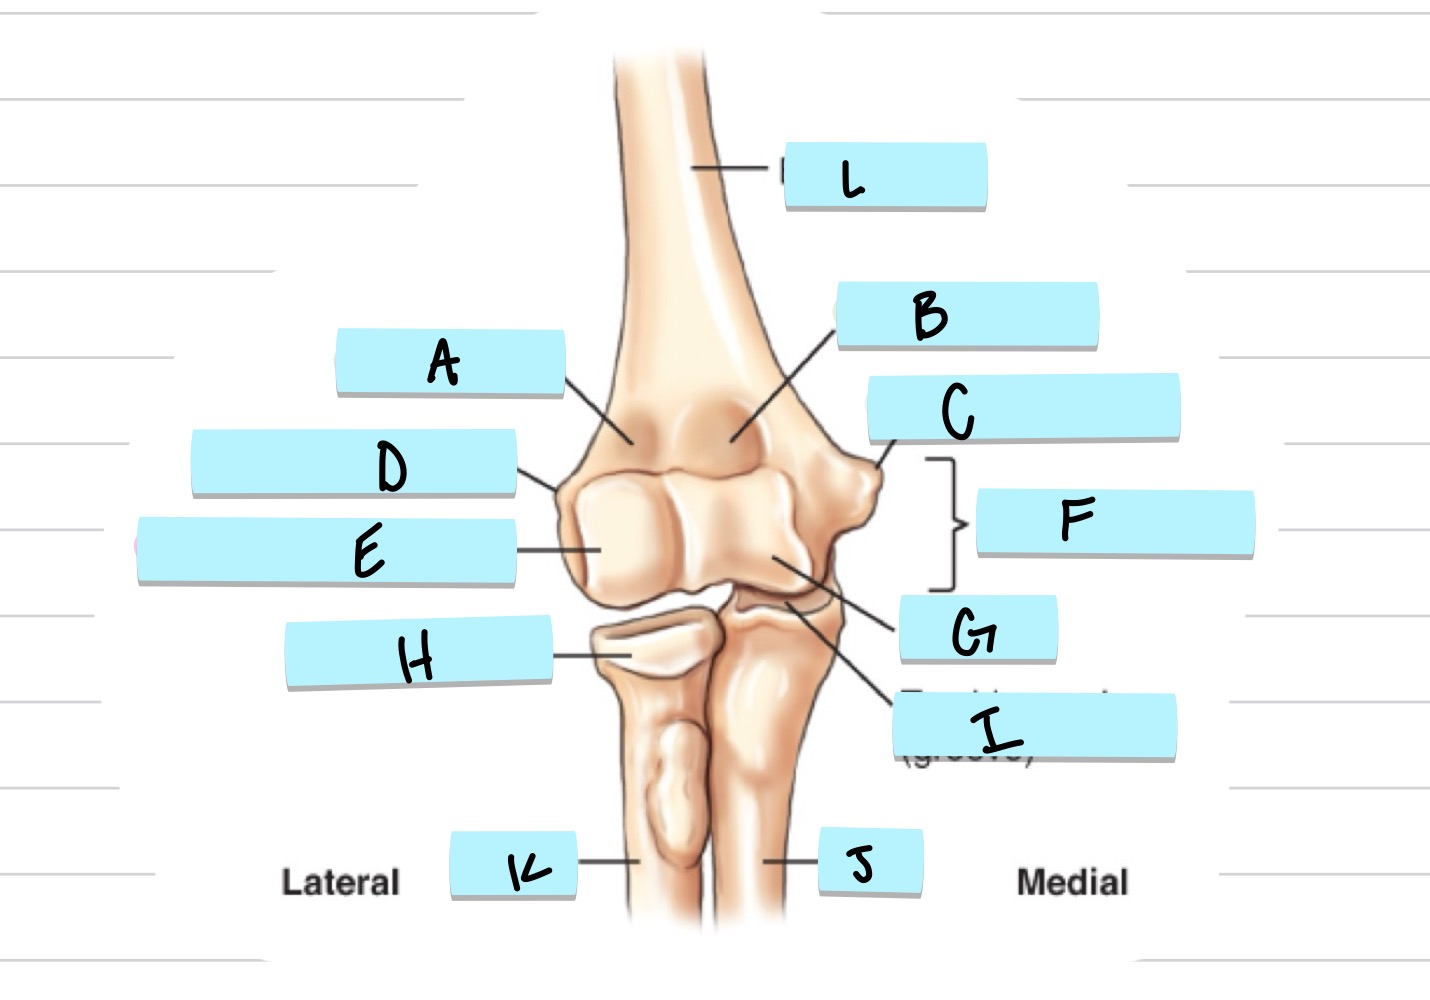

<p>what is A?</p>

what is A?

radial fossa

<p>what is B?</p>

what is B?

coronoid fossa